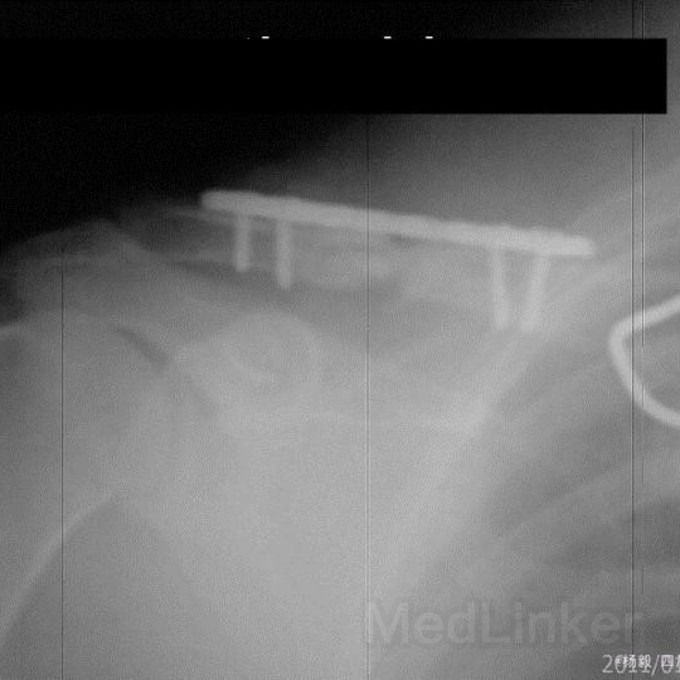

右锁骨粉粹性骨折内固定术后4月。因外伤致右锁骨粉粹性骨折,已行手术内固定4月,锁骨带固定近两月。术后四十天,锁骨内侧伤口红肿破溃,有肉芽形成,伤口约0.5cm大小,能探及钢板,一直门诊换药,现伤口未愈。请教诸位:目前采取积极态度清创后植骨内固定,还是保守治疗,要不要继续外固定?请各位发表高见。